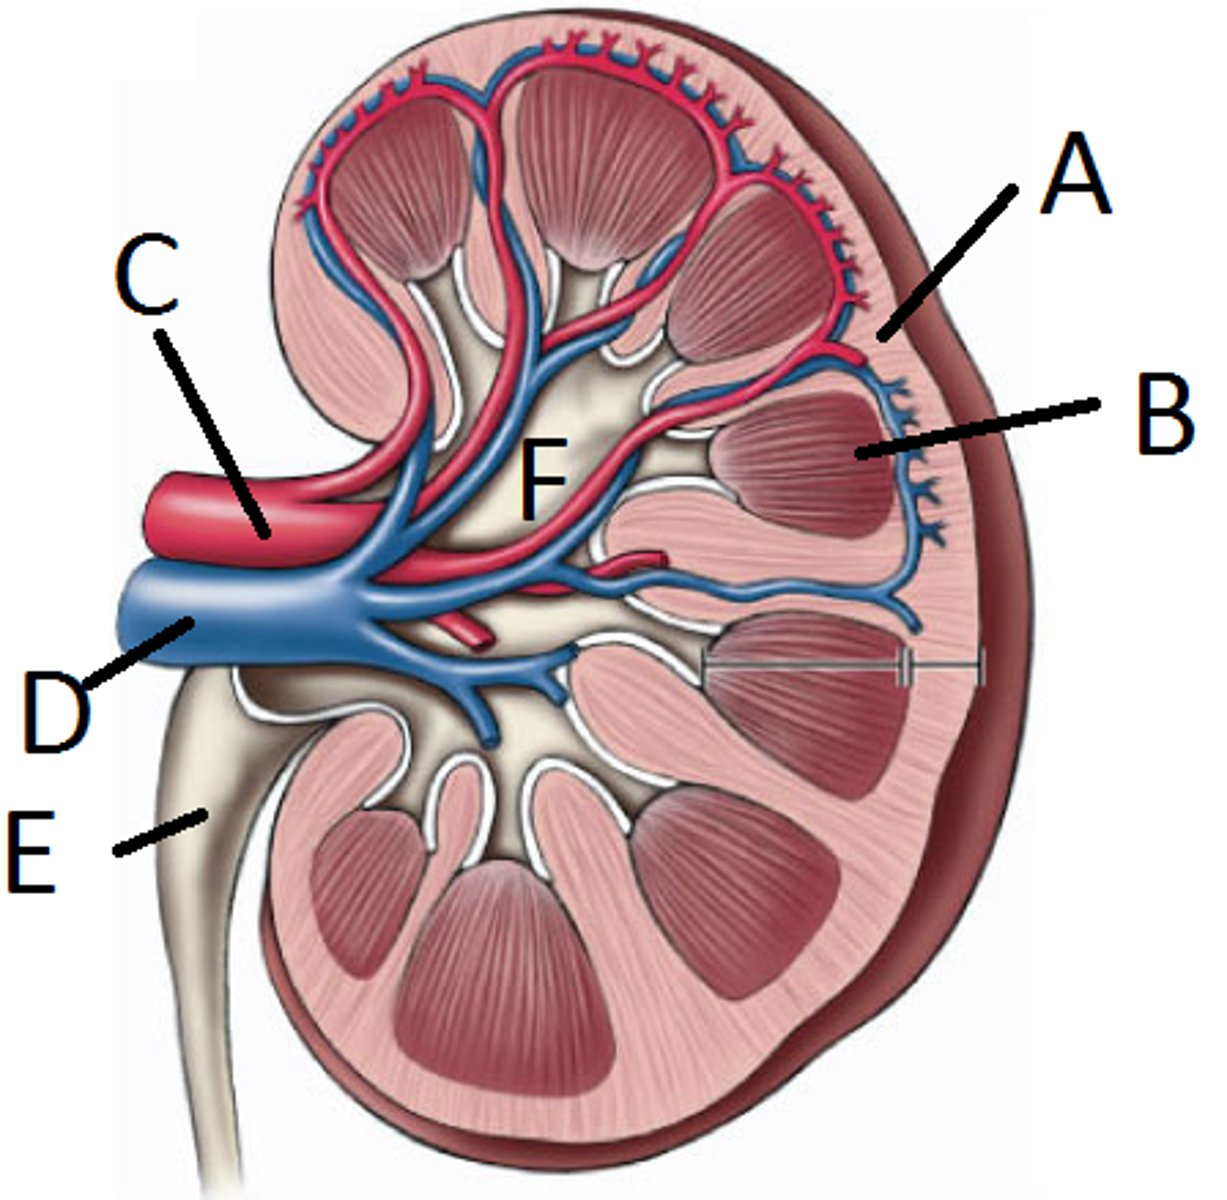

renal artery

C

renal vein

D

segmental

both vessels

interlobar

both vessels

interlobular

both vessels

arcuate

both vessels

E